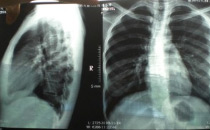

髋关节

例子

病症描述:(图1)腰椎1-5呈竹节样表现,(图2)髋关节钙化.脊柱弯曲困难间隙变小.(图3)髋关节间隙变小钙化。